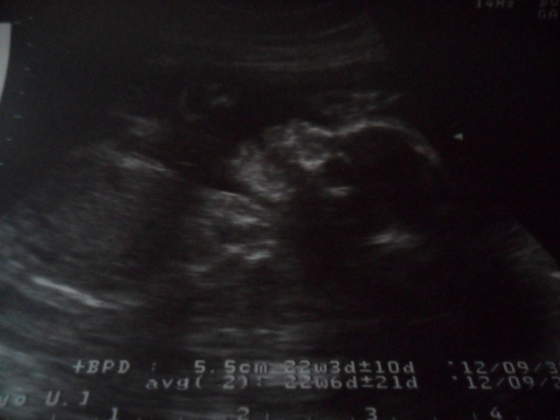

Zaanetkaaa mój też od razu mówił żeby się zapisać na dodatkowe usg żeby mieć "pewność" na kogo czekamy. Ja ciągle oglądam materiały w internecie i jakoś nie wierzę w tego chłopca